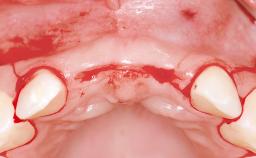

In November 2010, a 44-year-old woman presented to the Harvard School of Dental Medicine seeking options to replace her failing six-unit conventional prosthesis. Having served for approximately 10 years, the fixed partial denture had repeatedly needed recementation after chronic dislodgement over the past few months. Following these episodes, the patient requested further evaluation of her current prosthesis and showed interest in exploring other options for a fixed solution. The patient was in good overall health, presenting with no systemic contraindications to implant therapy or any history of allergies; she did not smoke and was on no medications. Being a well-motivated individual, she regularly saw her general dental practitioner and effectively complied with oral hygiene requirements.